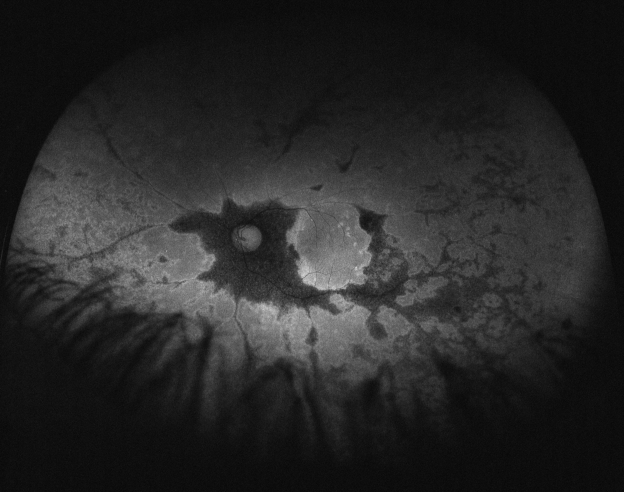

His best corrected visual acuity (BCVA) was 20/32 (Snellen chart) in his right eye (OD) and 20/63 in his left one (OS). Anterior segment was unremarkable for both eyes (OU). Fundus evaluation showed pigment clumps along the retinal veins with variable chorioretinal atrophy extending from the disc up to the equator in both eyes (clinically more evident in OS). Fundus autofluorescence (FAF) imaging revealed hypo-autofluorescent areas corresponding to the atrophic patches over the posterior pole (Figure 1 [Fig. 1] and Figure 2 [Fig. 2]). SS-OCT showed a preserved foveal profile and great macular atrophy in OU, but serious involvement of the retinal outer layers in the left eye (Figure 3 [Fig. 3] and Figure 4 [Fig. 4]). In Angio-OCT, severe involvement of the ellipsoid, choriocapillar, and avascular layers could be appreciated in OS.

Figure 1: Autofluorescence image of the right eye showing hypoautofluorescence at the paravenous zone

Figure 2: Autofluorescence image of the left eye demostrating hypoautofluorescence at the paravenous zone

Hypofluorescence in FAF shows the atrophy or disappearance of RPE because of a lipofuscin loss in RPE. Indeed, hypofluorescence detected by FAF corresponded to the areas of retinal thinning and atrophy detected using FA, IA, and OCT. In contrast, hyperfluorescence shows dysfunction of RPE that accumulates lipofuscin in RPE, suggesting the possibility of RPE atrophy in the future [9]. In the case that we present, paravenous hypoautofluorescence could be appreciated.